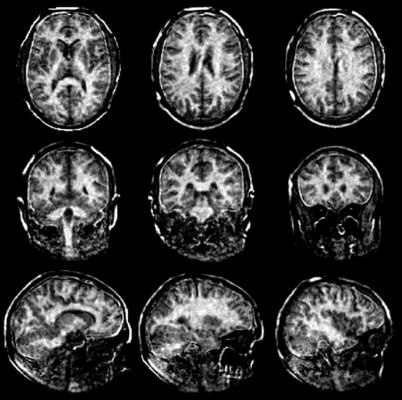

Improved MRI scans of the myelin sheaths in the brain should allow multiple sclerosis to be detected at an early stage. Image courtesy of ETH Zurich

The ETH researchers’ new MRI method solves this problem and measures the myelin content directly. It puts numerical values on MRI images of the brain to show how much myelin is present in a particular area compared to other areas of the image. A number 8, for instance, means that the myelin content at this point is only 8 percent of a maximum value of 100, which indicates a significant thinning of the myelin sheaths. Essentially, the darker the area and the smaller the number in the image, the more the myelin sheaths have been reduced. This information ought to enable doctors to better assess the severity and progression of MS.